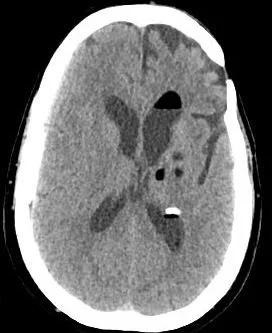

A 62 y.o. male with a hx of previous resection of a benign brain tumor comes to the ED with headache and fever.

what do you notice on his CT?

Our patient had a ruptured dermoid cyst with a lipid/fluid interface in the ventricle.  Dermoid cysts are present at birth and occur when ectoderm  layers don’t grow together normally. They contain remnants of ectodermal tissue including sebaceous cysts, oil producing  hair follicles, squamous epithelium and sometimes teeth.  They most commonly present in the first three decades of life. Dermoids are the most common pediatric tumor and are found in the orbit and periorbital areas often over the L eyebrow.

the lipid/csf interface from a ruptured dermoic

In the brain dermoids account for <1% of all intracranial masses They are most commonly found in the midline because they are felt to be ectopic ectoderm from the neural tube. They are often in the suprasellar cistern.  As they grow they are at risk for rupture and serious complications such as chemical meningitis, vasospasm and infarct can occur.

An unruptured dermoid presents as a fatty lesion in the brain.